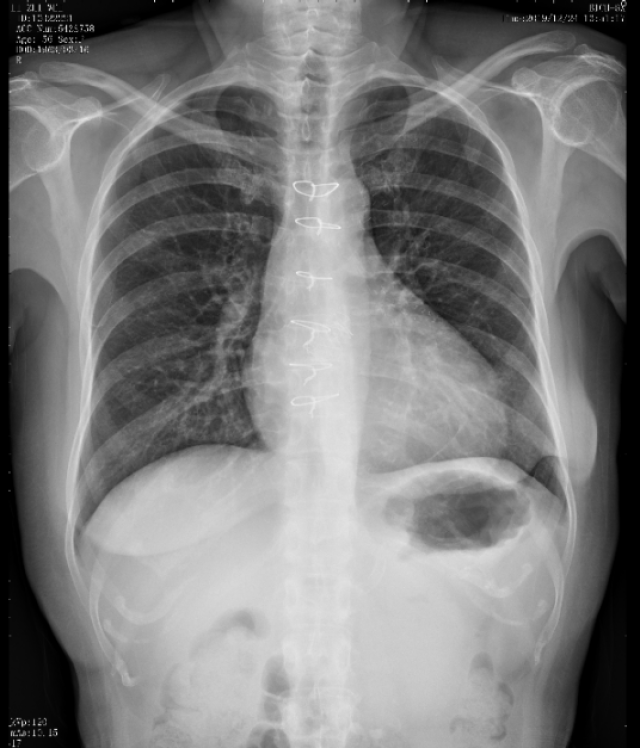

胸部X线:

双肺渗出,心影增大,心胸比:0.60,双侧胸腔积液。